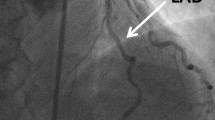

The PET scan protocol has been described previously [18, 19]. Pharmacological stress was induced by adenosine triphosphate (ATP) infusion at a rate of 0.16 mg kg−1 min−1 for 8 min through the left antecubital vein [20, 21]. MBF at rest and during ATP infusion was calculated by 15O-labelled water PET (Fig. 1). All the PET scans were obtained with an ECAT EXACT HR+ (Siemens/CTI).

In brief, a transmission scan was performed to correct photon attenuation for 6 min with a 68Ge source. Next, all the subjects inhaled 15O-labelled CO for 1 min to obtain the blood volume image. The total inhaled dose was 2,000 MBq. Then 15O-labelled water was infused into an antecubital vein to obtain the blood flow image. The administered dose was 1,000 MBq. Twelve minutes after the first infusion of 15O-labelled water, intravenous ATP infusion (0.16 mg kg−1 min−1) was started and PET acquisition was commenced 3 min after the beginning of ATP infusion. ATP infusion was continued until the end of the second 15O-labelled water PET scan. Heart rate, blood pressure and 12-lead ECG were recorded at rest and at 1-min intervals during and after the ATP administration.All the emission sinograms were reconstructed with filtered back-projection using a Hann filter (cut-off frequency, 0.3 cycles/pixel). The in-plane resolution was 4.5 mm in full-width at half-maximum in the images reconstructed into a 128×128 matrix. All the data were corrected for dead time, decay and measured photon attenuation.MBF was quantified using the single tissue compartment model developed by Katoh et al. [22]. The left ventricle was divided into three regions according to coronary artery regions (Fig. 2) and regional MBF was calculated in each region. Regional MFR was calculated as the ratio of regional hyperaemic MBF to regional MBF at rest. Two experienced doctors blind to the patients’ clinical data analysed all the PET data.